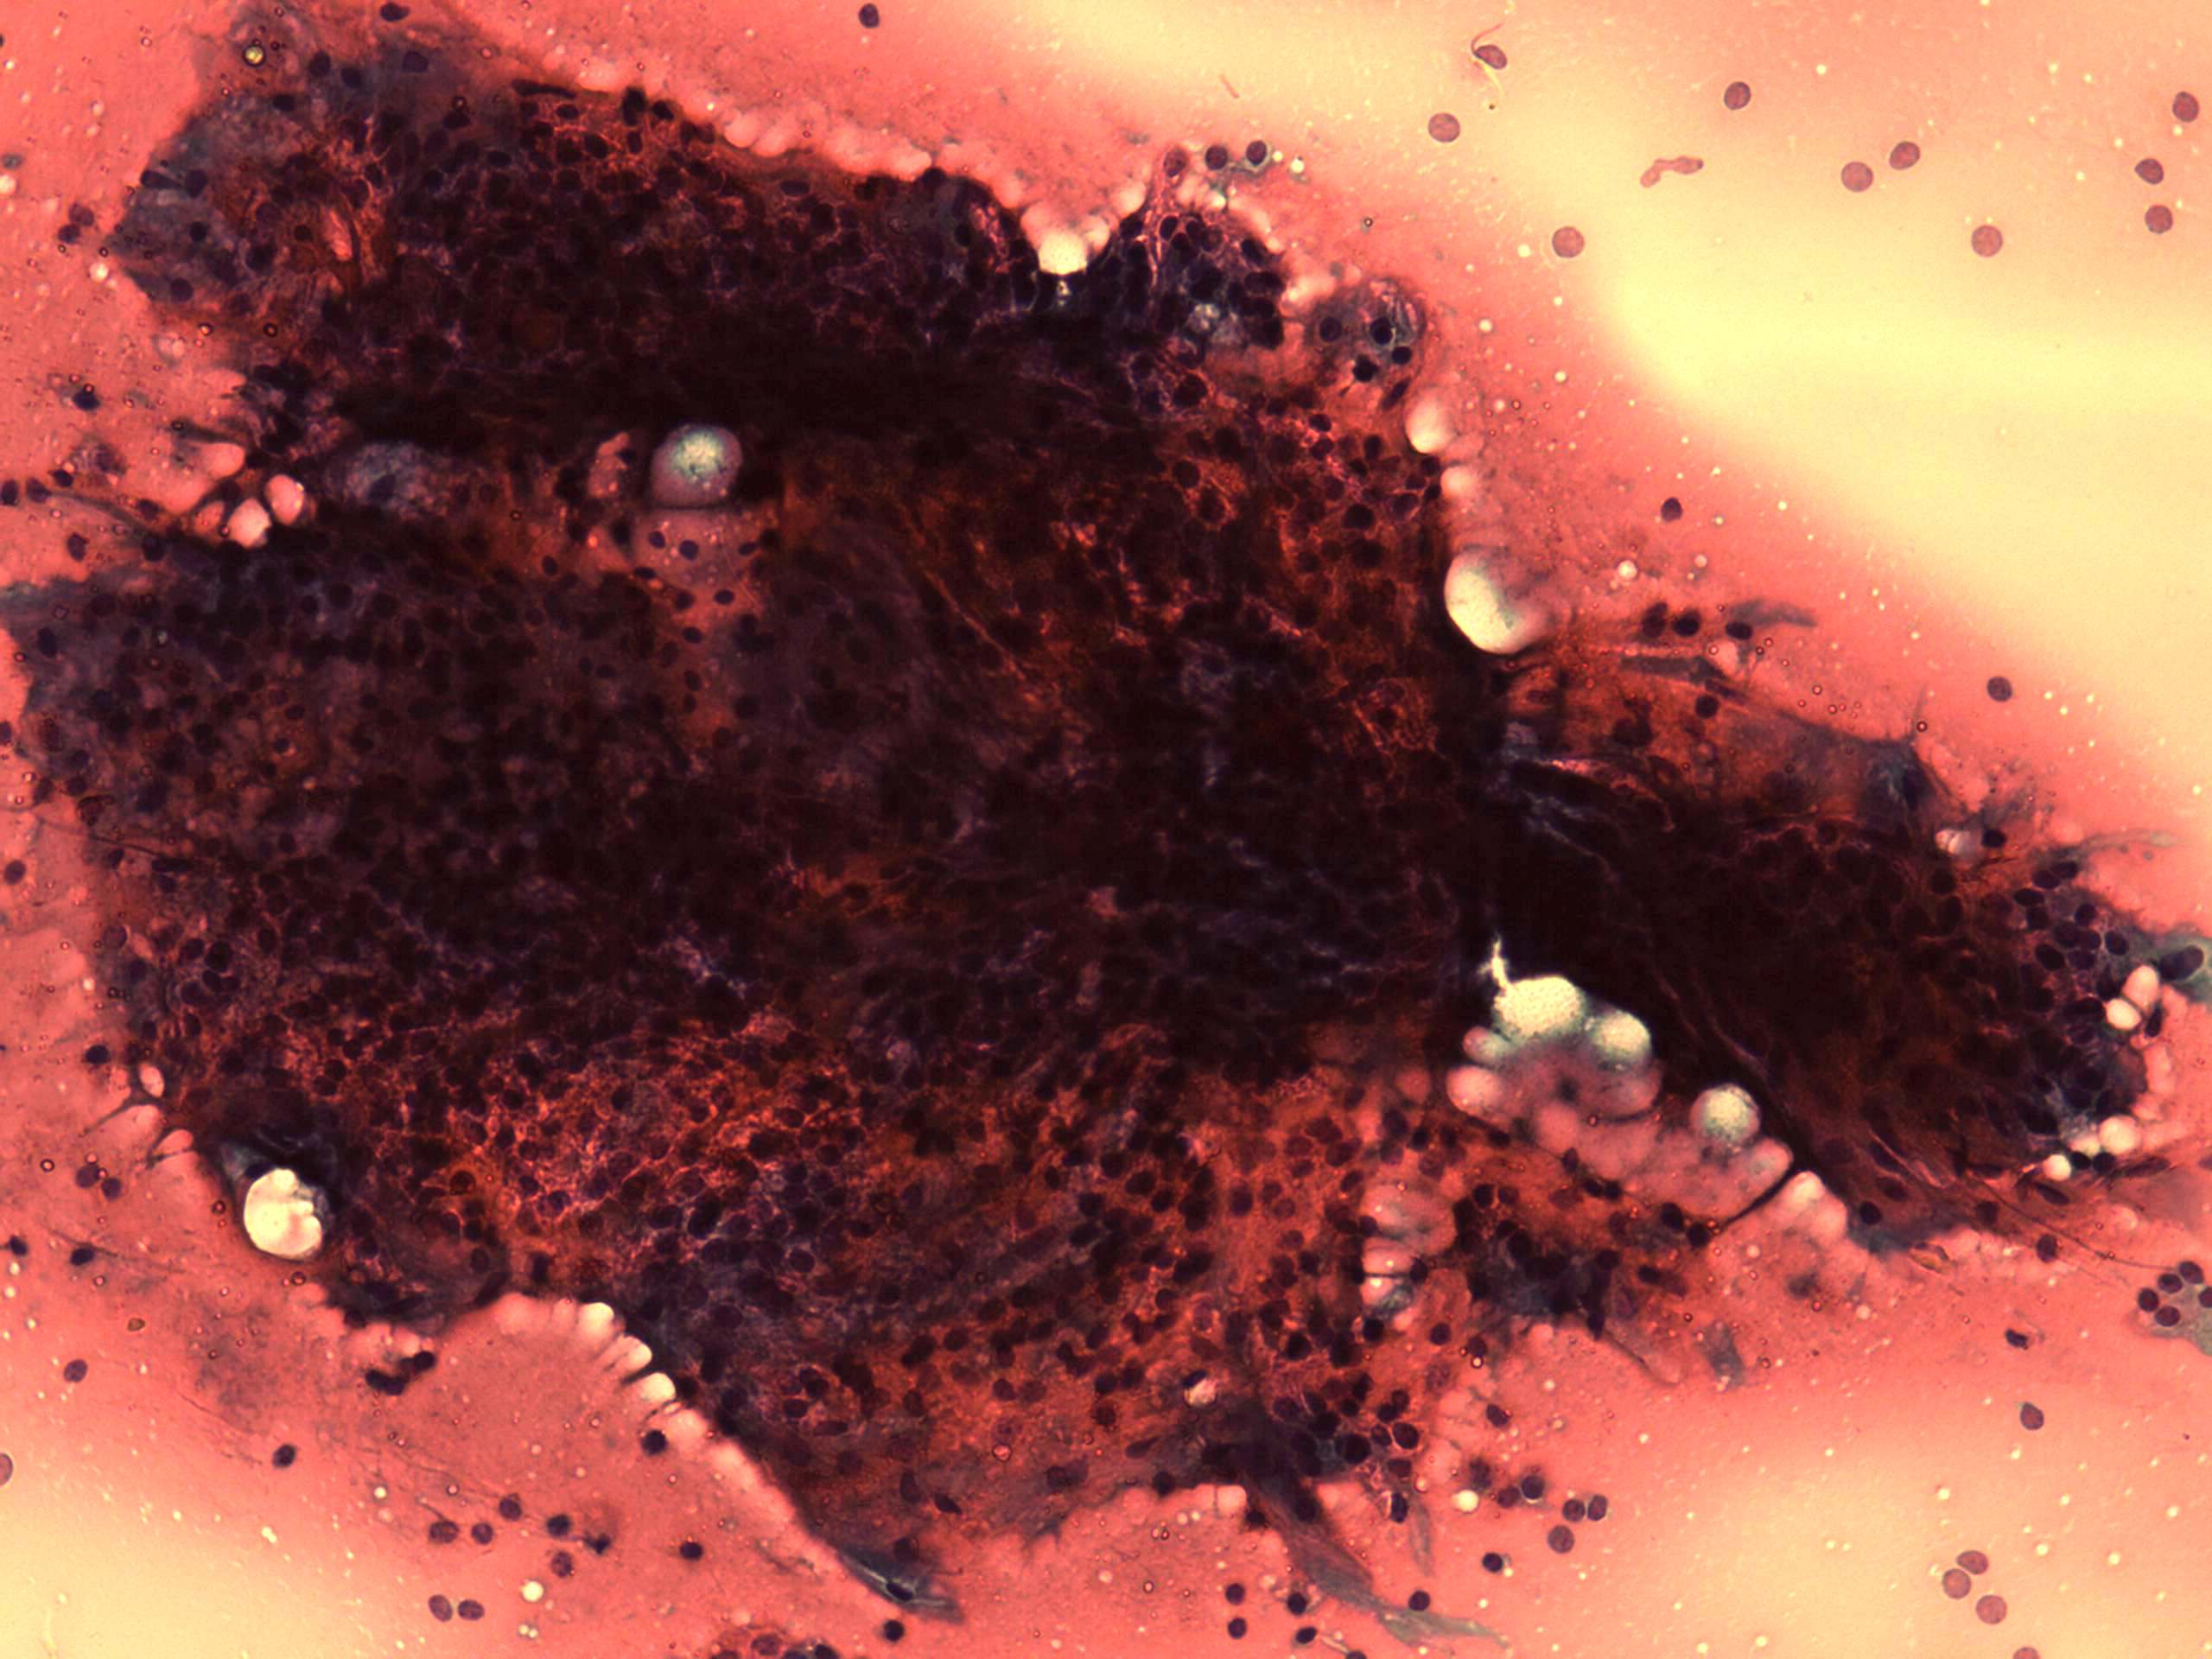

Benign nodular hyperplasia - Case 38. (cytologic picture 3)

Pap-smear, 200x. Note the peripheral vacuolization.